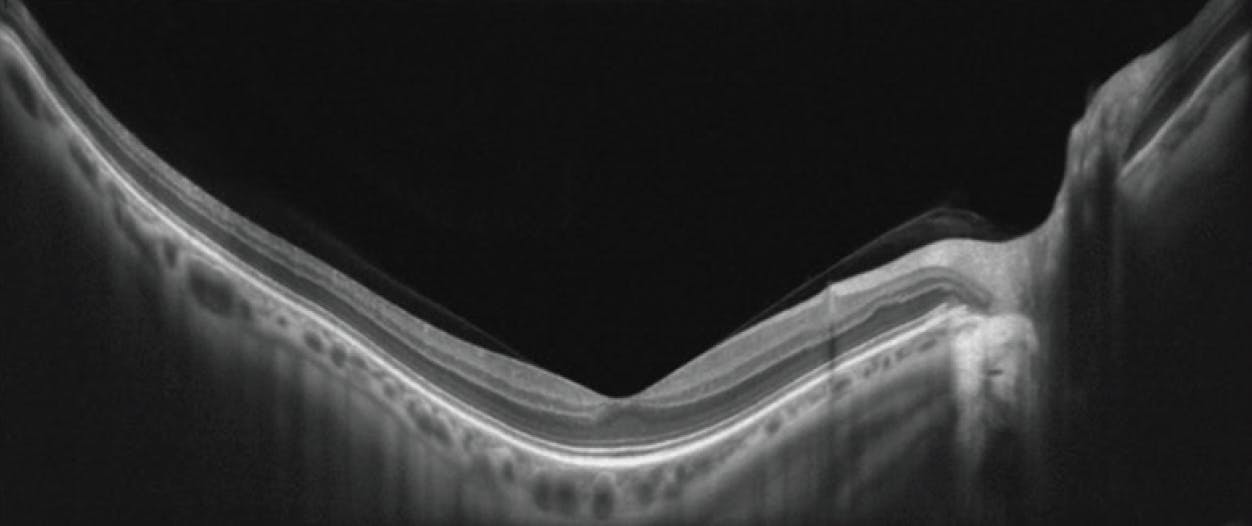

An anomalous PVD occurs when vitreous liquefaction or contraction outpaces the detachment of the vitreous cortex. The International Vitreomacular Traction Study Group defines an anomalous PVD as a partial vitreous detachment with persistent attachment in the macular region.6 Various vitreomacular interface disorders manifest as a result of an anomalous PVD.7,8 VMA involves a perifoveal vitreous detachment and is synonymous with a stage 1 PVD or detachment of the vitreous in the perifoveal region. VMA is defined strictly by the anatomic features seen on OCT (Figure 2). The cortical vitreous is elevated above the retina, but there is no change to the retinal anatomy within a 3 mm radius of the fovea.